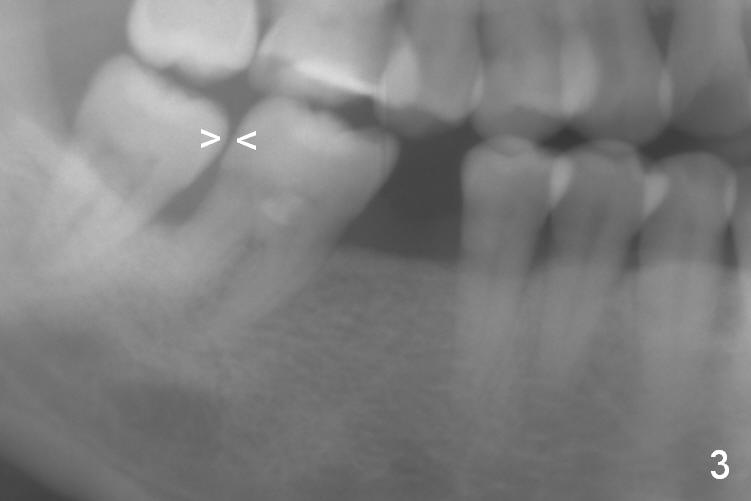

A 47-year-old lady has lost the lower right 1st molar for long time; with reduction of the buccolingual width (Fig.1) and mesiodistal width (Fig.2,3). With regional orthodontic appliance (Fig.4) for 3 months, the tooth #29 has started being distalized (Fig.5). One month and a half later, the tooth #26 starts to shift labially. Power chains and then closed coil spring are placed between #29 and 32. #29 distalization is slow (Fig.7) with closure of the diastema between #31 and 32 (Fig.8, as compared to Fig.1,3). Seven months post banding, a 10 mm miniimplant is placed distobuccal to the tooth #32 (Fig.6); the same 12-mm closed spring is stretched distal by ~ 6 mm (Fig.8 between arrowheads). Two months later, #29 is more distalized (Fig.9 tilted) with bone deposit mesially (*) and coronally (^). A .018' stainless steel wire is installed with an open coil spring placed between #28 and 29 (Fig.10 (^),11). Note #29 rotation (Fig.11). To solve the tilting, a power hook (Fig.12 black) will be clamped to a .016x.016 wire (red), while the closed spring is lowered and attached to the power hook (Fig.12 white). Take photos after removing the existing wire occlusally to show the alveolar width change. When the wire is placed, make sure that the distal wings of #29 bracket is fully engaged to reduce the tooth rotation. Make occlusal adjustment on #31 and 32 to reduce anterior open bite.